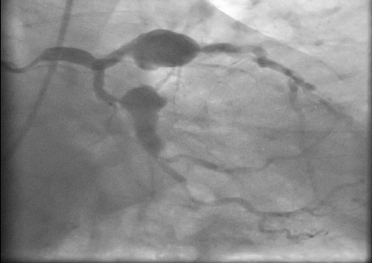

Multiple Giant Coronary Arterial Aneurysms Leading to Stable Angina

Coronary artery aneurysm (CAA) is defined as abnormal dilatation of a coronary artery luminal diameter to 1.5 to 2 times wider than the adjacent normal segment. Giant coronary artery aneurysms are rare, with a reported prevalence of 0.02% to 0.2% [1].